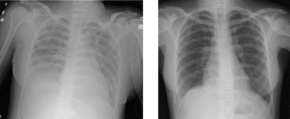

In medicine, transfusion related acute lung injury (TRALI) is a serious blood transfusion complication characterized by the acute onset of non-cardiogenic pulmonary edema following transfusion of blood products.[1]

It is often impossible to distinguish TRALI from adult respiratory distress syndrome. The typical presentation of TRALI is the sudden development of dyspnea, severe hypoxemia (O2 saturation <90% in room air), hypotension, and fever that develop within 6 hours after transfusion and usually resolve with supportive care within 48 to 96 hours. Although hypotension is considered one of the important signs in diagnosing TRALI, hypertension can occur in some cases.